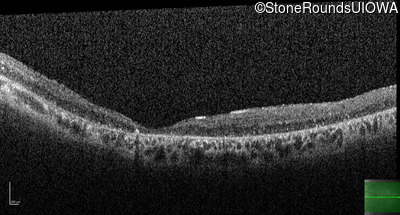

Age at visit: 41 years

This 41 year old man first came to medical attention at age 18 months when exotropia and amblyopia of his right eye were discovered. At age 11 vitreous strands and retinal vascular sheathing were seen. He has had poor night vision and constricted visual fields since his late teens. Later, at age 44 a traction retinal detachment was noted in his left eye and was treated with a scleral buckle.